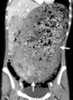

Severe gastric dilatation

Gastric outlet obstruction (GOO) is a medical condition where there is an obstruction at the level of the pylorus, which is the outlet of the stomach. Individuals with gastric outlet obstruction will often have recurrent vomiting of food that has accumulated in the stomach, but which cannot pass into the small intestine due to the obstruction. [Source: Wikipedia ]